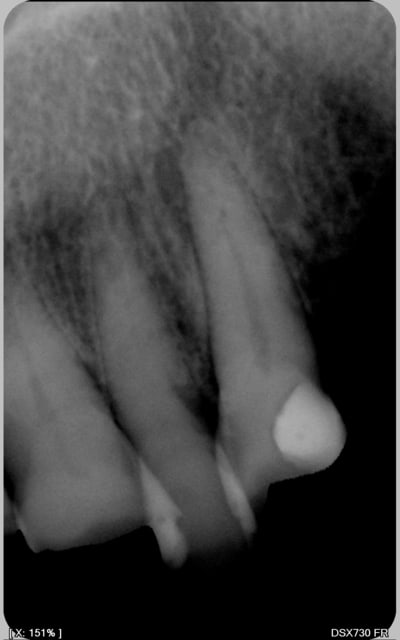

encore des radios,peut-etre assez moyen comme traitement...mais je vu pire...

les dernieres radios. patient en urgence ,abces... il voulait pas extraire la dent. j'ai lui bien explque et il a choisi de essayer de garder la dent. retrait,pas d'isolation avec la digue donc pas de tenon fibree,amalgam et screw post.traitement fait il ya 2 ans je crois.patient fidel de cabinet maintenent.